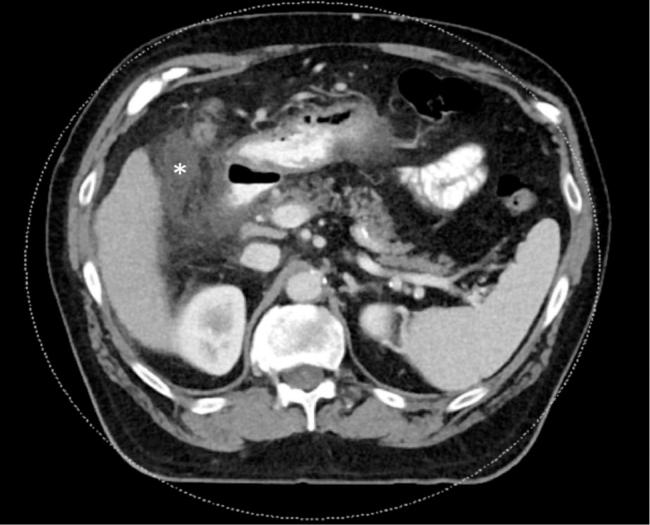

61-year-old male with history of pulmonary fibrosis, cholecystectomy and Hepatitis C underwent transjugular liver biopsy (TJLB) as part of his lung transplant workup. Shortly after the procedure, the patient developed sharp right upper abdominal pain. Immediate CT of the abdomen and pelvis showed small foci of contrast and gas in the gallbladder fossa and porta hepatis indicating hepatic capsular penetration without perihepatic hematoma or other evidence of hemorrhage. Follow up CT of the abdomen and HIDA scan confirmed the presence of bile leak. Sphincterotomy and stent placement through ERCP was performed.

一名61岁男性,有肺纤维化、胆囊切除术和丙型肝炎病史,作为其肺移植检查的一部分接受了经颈静脉肝活检(TJLB)。术后不久,患者出现右上腹剧痛。腹部和盆腔的即时CT显示胆囊窝和肝门处有小的造影剂和气体灶,提示肝包膜穿透,但无肝周血肿或其他出血迹象。腹部随访CT和HIDA扫描证实存在胆漏。通过内镜逆行胰胆管造影(ERCP)进行了括约肌切开术和支架置入术。